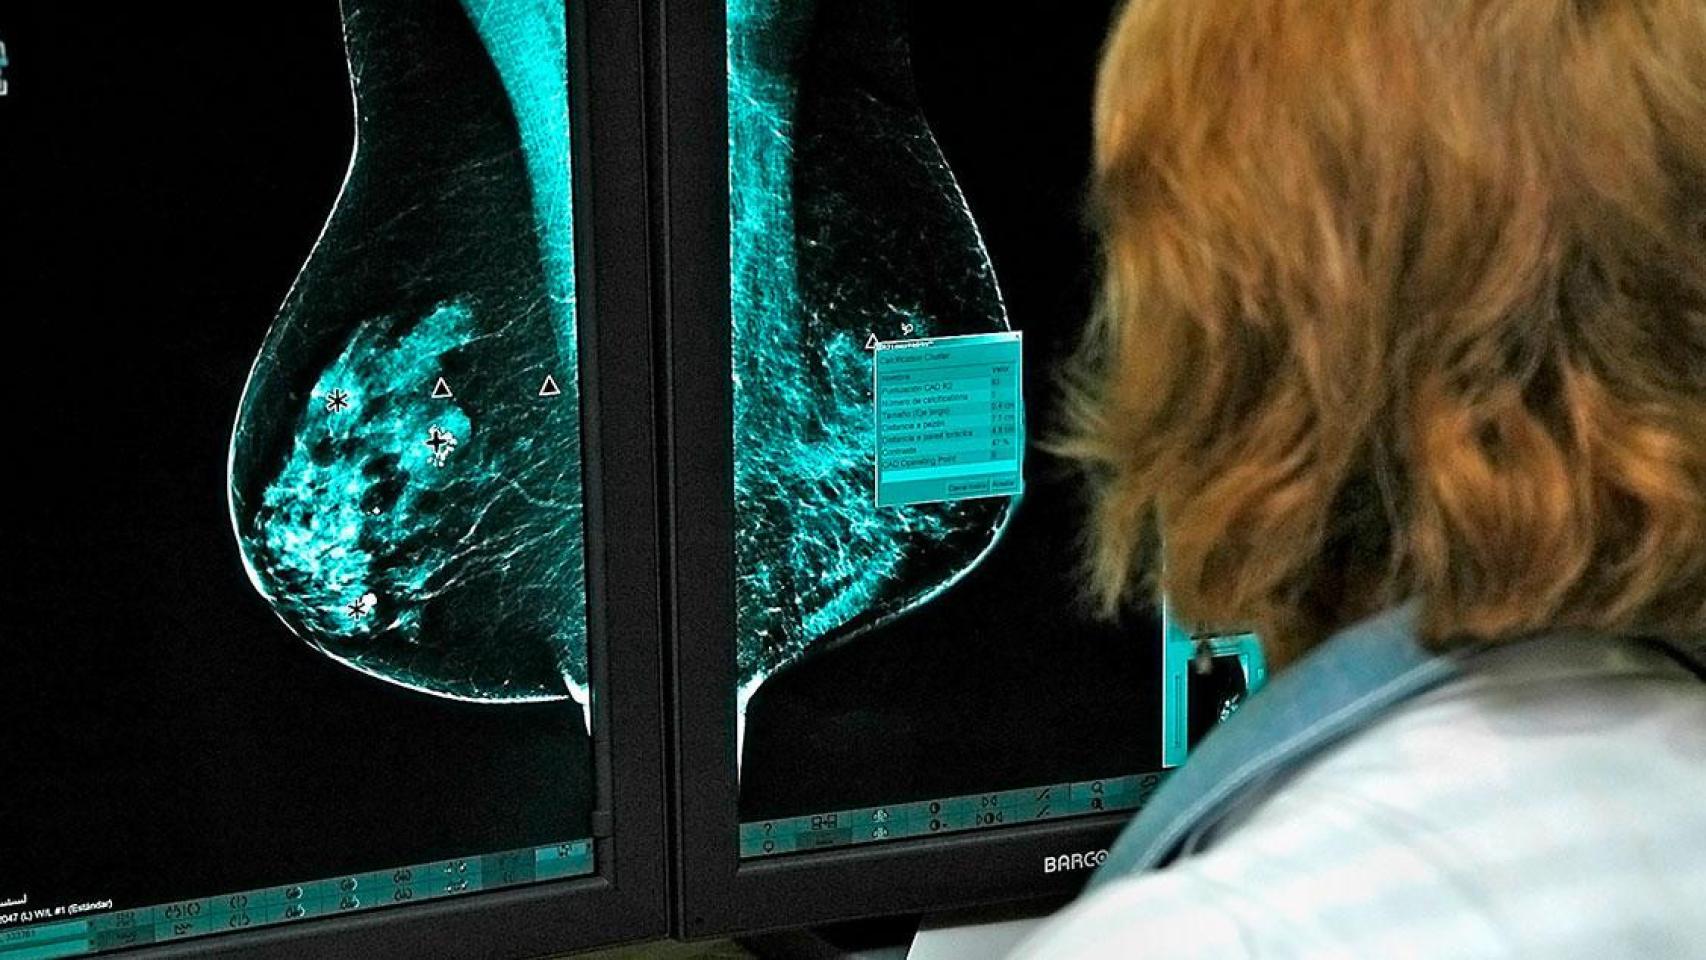

Una mujer se trata de su cáncer de mama en un hospital CG